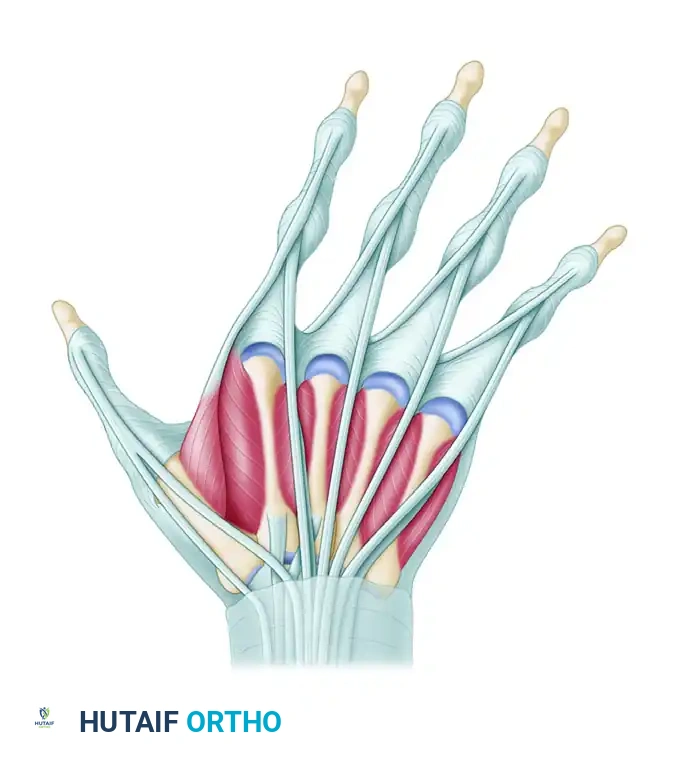

- Intrinsic Muscle Imbalance: The ulnar-sided intrinsic muscles (abductor digiti quinti and flexor digiti quinti) possess greater cross-sectional area and contractile strength than their radial counterparts (e.g., the third volar interosseous).

- Intrinsic Contracture: Chronic inflammation leads to interosseous muscle contracture. This intrinsic tightness causes profound ulnar deviation and PIP joint hyperextension (initiating a swan-neck deformity), alongside MCP joint flexion and eventual fixed subluxation.

* Intrinsic Release or Transfer: Release of the tight ulnar intrinsic insertions (e.g., the ulnar lateral band of the index finger) to eliminate the deforming pull. In some cases, the released ulnar intrinsic tendon can be transferred to the radial aspect of the adjacent ulnar digit to augment radial stability (crossed intrinsic transfer).